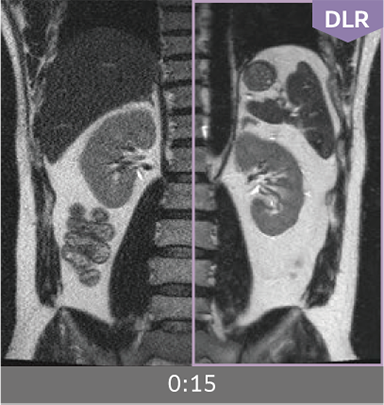

Combining high-speed imaging technology with Deep Learning reconstruction technology*3, Advanced Reconstruction with Deep Learning Synergy DLR, enables shorter exams and reduces image noise.

Images can be obtained at high speed by combining two proprietary technologies: IP-RAPID, which reduces imaging time while maintaining image quality, and Synergy DLR, which uses deep learning technology*6 to improve image quality

Under-sampling reduces imaging time, and iterative reconstruction with IP-RAPID reduces noise and artifacts.

In addition, Synergy DLR, an image reconstruction technology utilizing deep learning technology, further eliminates noise and produces images that are easier to use in making a diagnosis.